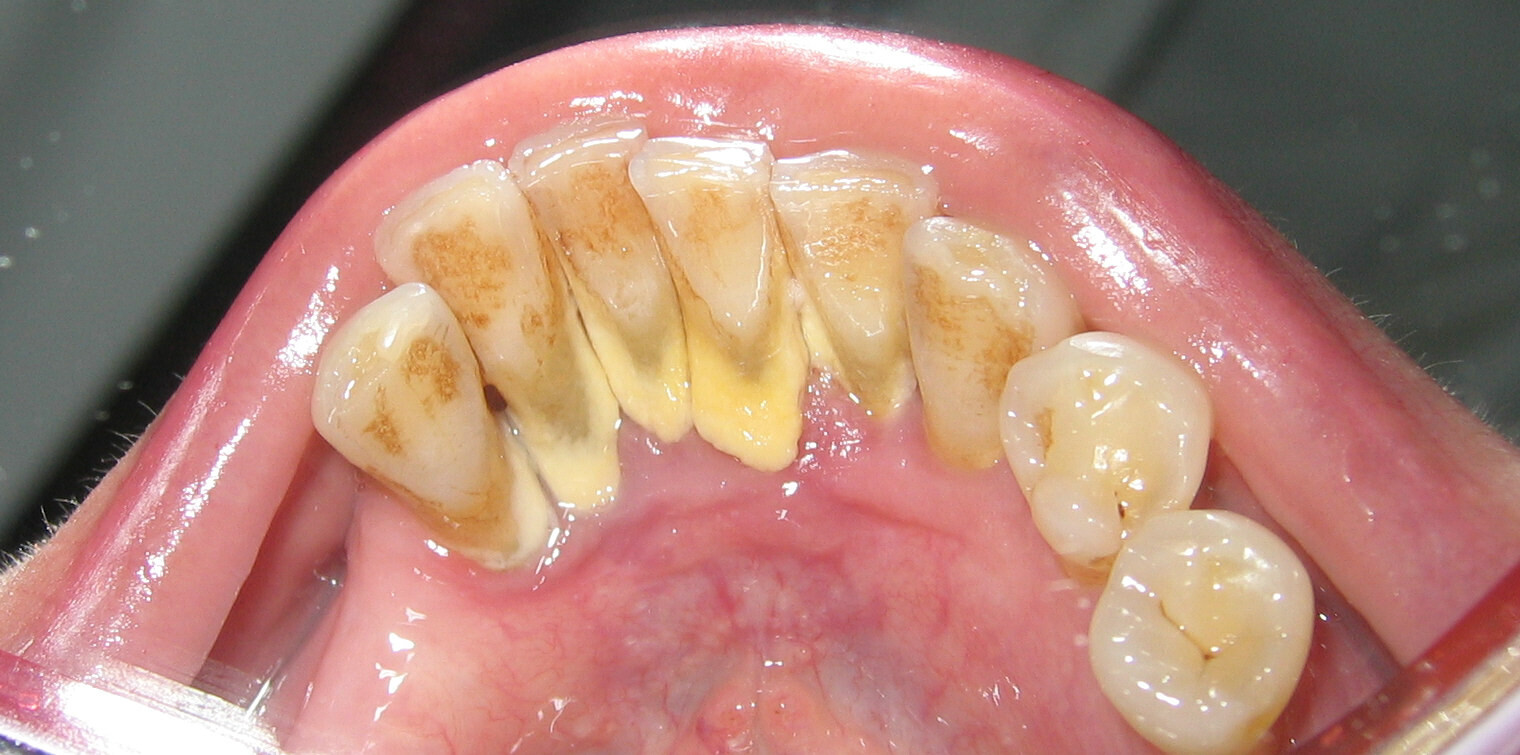

According to the IJDHS review, there are two types of dental calculus: supragingival and subgingival. The difference between the two types is the location of the calculus relative to the edge of the gum tissue.

If you think of the edge of the gums like a shirt sleeve and imagine the tooth is like your hand in the sleeve, you can get a better image of this classification. The parts of your hand and wrist that extend visibly outside the sleeve would be considered supragingival (above the gumline), whereas anything unseen below the sleeve would be considered subgingival (below the gumline). Calculus above the gumline can appear whitish or yellowish in color.

Removing Supragingival Calculus

While your dentist and dental hygienist can typically detect supragingival calculus visually, dental professionals also receive extensive training using equipment other than their eyes. One such example, according to the IJDHS review, is an instrument known as a dental explorer, which helps the dental professional feel and remove calculus. A scaler is another common handheld instrument used to remove calculus above the gumline, as a review in the Saudi Dental Journal notes. In addition to these, new technologies — such as ultrasonic and laser tools — have also emerged to help dentists and hygienists detect and remove calculus.

It's important to remove calculus as soon as it's detected to prevent further bacteria buildup and retain gum health. The ADA notes that as supragingival calculus develops, the gums can become swollen and bleed easily. This condition, termed gingivitis, can worsen into a more serious form of gum disease if left untreated.